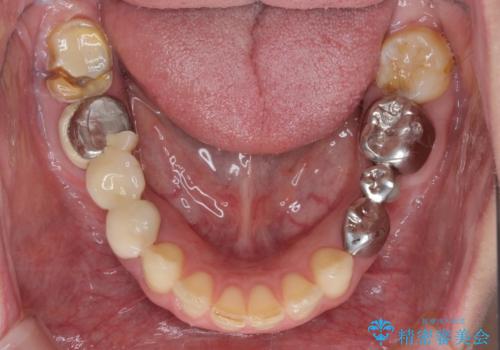

- 近医で奥歯が割れているので抜歯が必要と言われたとのことで来院された患者様です。

診断の結果、歯根が縦に破折しており抜歯が必要な状態でした。

抜歯してからインプラント埋入までには時間がかかるため、その間に下顎左右臼歯の金属のブリッジをオールセラミックへ変えていくこととしました。

目立つ部分の銀歯や気になる変色歯をまとめてきれいに仕上げることができました。